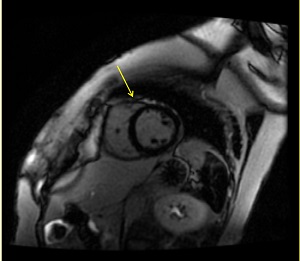

Figure 2. Image from a 2D multi-slice, single breath hold, Single Shot, FIESTA MDE at 3.0T with visible banding artifacts across myocardium